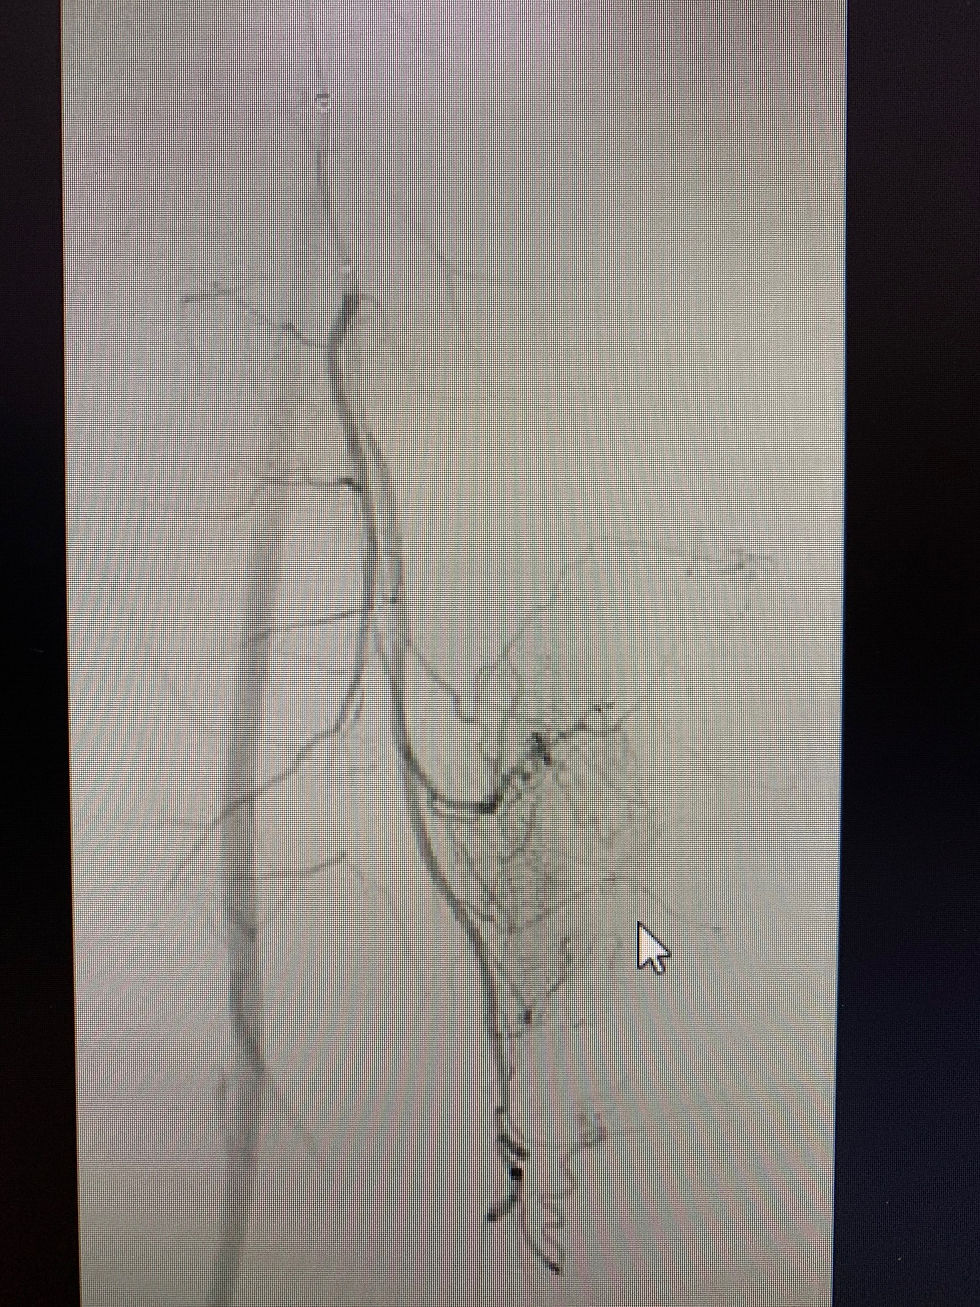

Angioplastia periférica